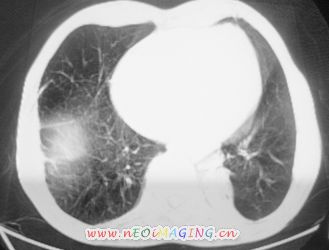

以下是引用卜一在2007-10-7 9:38:00的发言:[br]左下肺胸膜下团片影,内见含气支气管像,临近胸膜未见增厚。多考虑:1 左下肺炎症,建议消炎后复查!2 不除外肺隔离症合并感染!